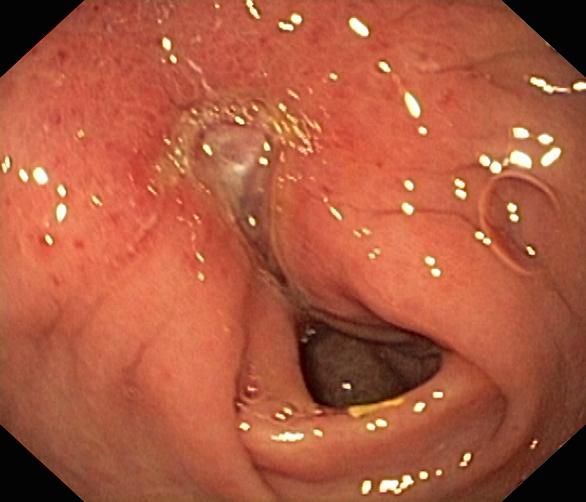

Wrzód trawienny